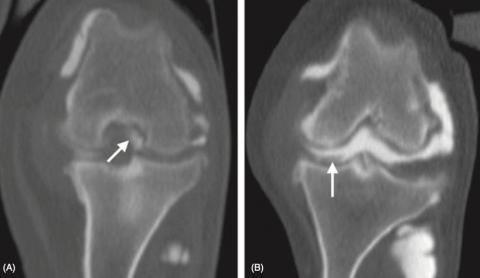

Ruptura předního zkříženého vazu u psů

Kolenní kloub je komplexní a střídavý kloub, kde se střídá extenze a flexe (1). Je největší synoviální kloub v muskuloskeletálním sytému a skládá se ze tří kostí: femuru, tibie a patelly (1, 2). Dále se celý kloub dělí na dva samostatné, a to na articulatio femorotibialis a na articulatio femoropatellaris (1).